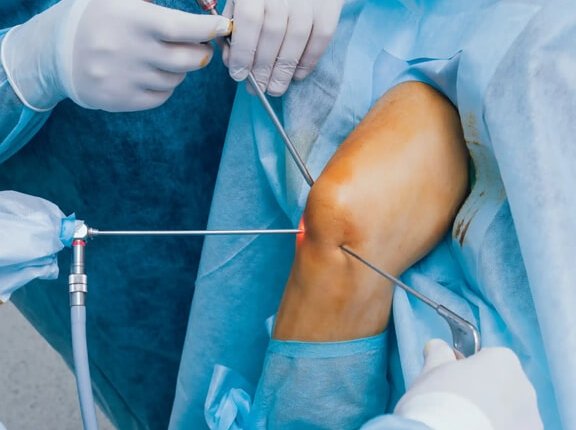

Dr. Shiva Shankaran GB is a senior specialist surgeon in knee and shoulder surgeries. He specializes in Sports injury, Arthroscopy, and Joint Replacement Surgeries. His journey is marked by a commitment to excellence and a relentless pursuit of knowledge. Physical Remedy and drugs are the first non-surgical options we look into when treating common pain, but if surgery is eventually necessary, we’ll give you the best treatment possible to help you return to your diurnal conditioning as soon as possible.

Arthroscopic & Replacement Surgeries